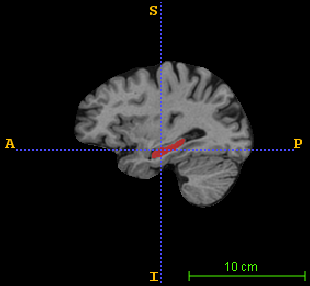

A validation study has been conducted on the brain MRI data drawn from the Alzheimer’s Disease Neuroimaging Initiative database (http://adni.loni.usc.edu). As a pilot study, 100 brain images were randomly picked: 34 healthy subjects, 33 with mild cognitive impairment (MCI) and 33 AD patients, with a demographic profile presenting no statistically significant difference on age and MMSE score from the whole database (pβˆ’v​a​l​u​e>0.1π‘π‘£π‘Žπ‘™π‘’π‘’0.1p-value>0.1). All images were bias-corrected and linearly aligned in the widely-used MNI152 template space. Each image also includes a reference manual segmentation of the hippocampus. A sample image superimposed with its label map is shown in Fig. 1.

Figure 1: A sample brain MR image superimposed with its hippocampus reference segmentation in (left) axial view, (middle) sagittal view, and (right) coronal view. The green and pink colored regions respectively indicate the left and right hippocampus